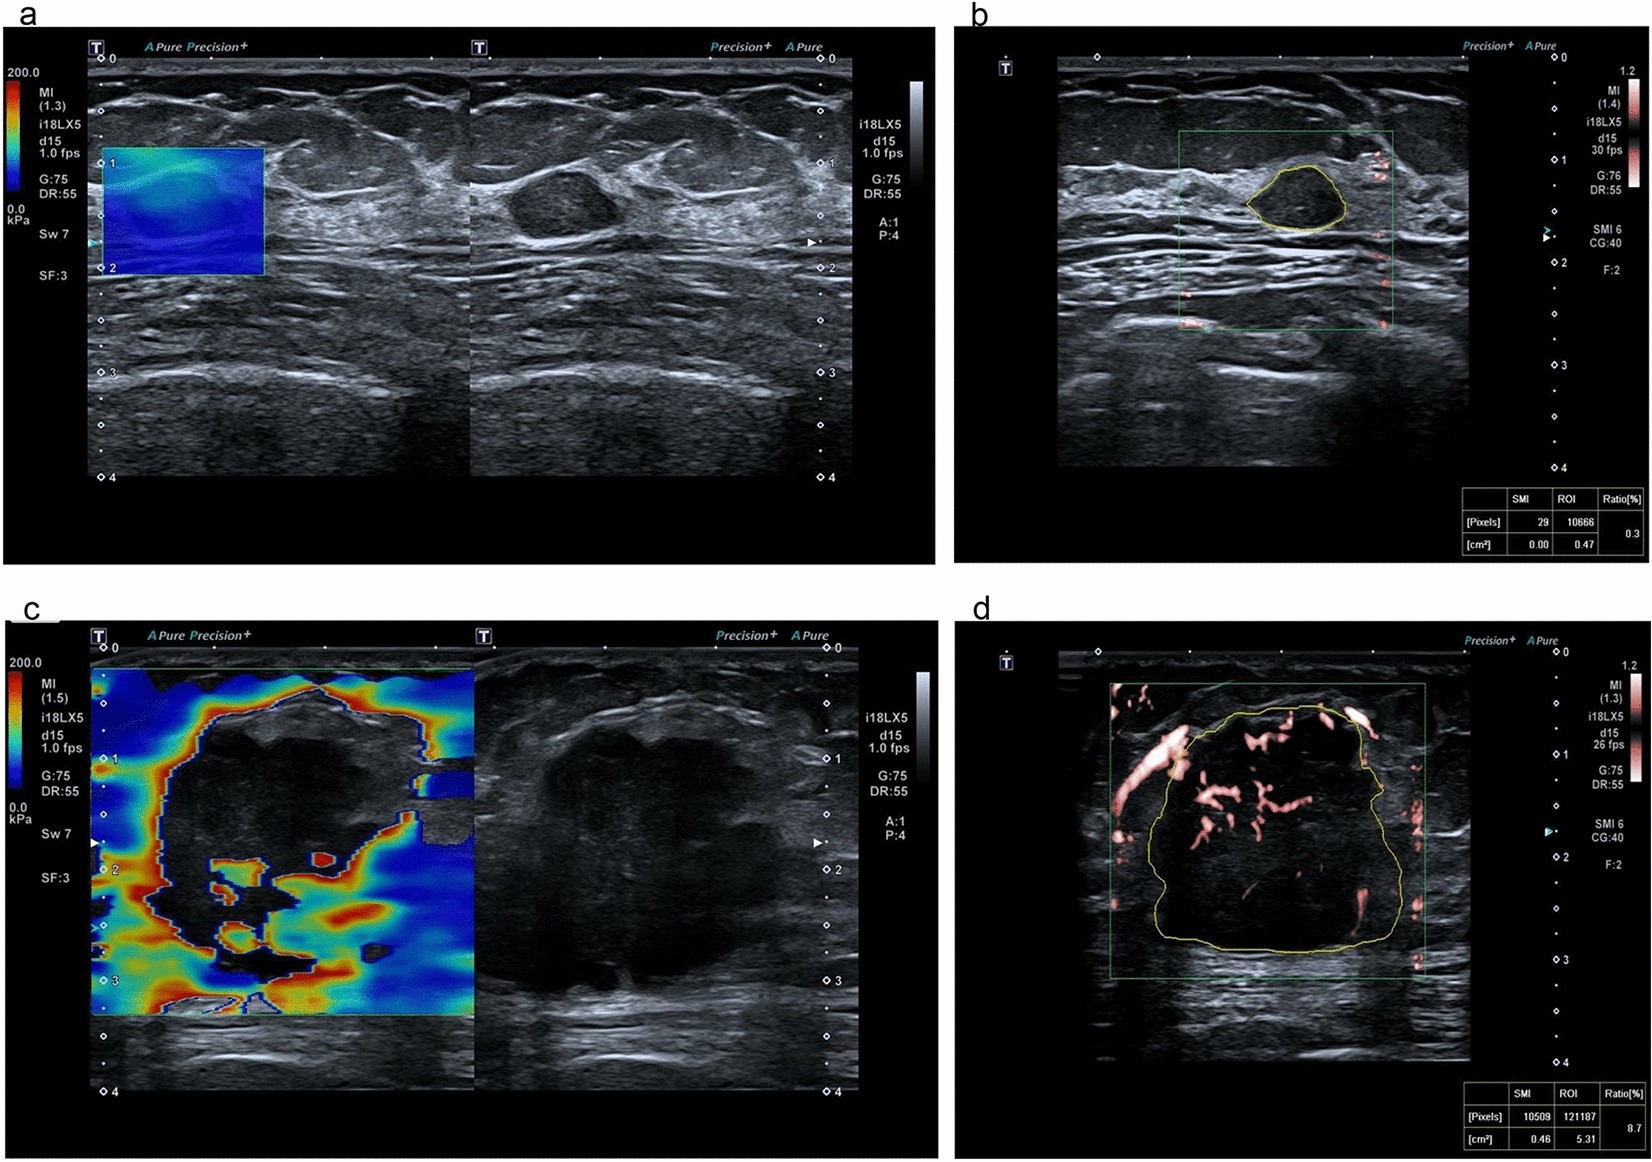

Figure 2

From: A ultrasonic nomogram of quantitative parameters for diagnosing breast cancer

Examples of SWE and VI ultrasound images. A benign lesion with SWE, (a) 32.8 kPa and VI 0.3%, (b) and a malignant lesion with SWE, (c) 159.7 kPa and VI 8.7% (d).